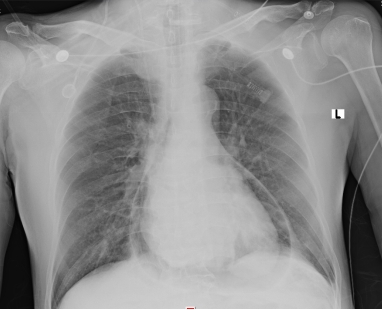

| 图 4 胸部正位片提示纵隔积气,心包积气 |

1 资料与方法患者男性,70岁,因“胸闷3 d,加重伴呼吸困难1 d”于2019年9月13日入外院。患者3 d前无明显诱因出现胸闷,伴全身乏力,夜间睡眠差(可平卧),初未予重视,1 d前胸闷加重,伴呼吸困难、运动耐量明显下降、大汗淋漓、皮肤湿冷,至外院就诊,查心电图(图 1):交界性逸搏,肢体导联低电压,Ⅰ、Ⅱ、Ⅲ、aVF、V4、V5、V6导联ST段抬高0.15 mV~0.4 mV,aVR、aVL、V1导联ST段压低0.05 mV~0.2 mV,aVL、V1导联T波倒置;心肌酶:CKMB 27.1 U/L,NT-proBNP 3 298 pg/mL。外院考虑不排除急性心肌梗死导致的心源性休克,经口气管插管接呼吸机辅助通气后为进一步诊治转入本院。患者家属否认患者有外科手术、外伤、气胸及哮喘发作史,起病以来无畏寒、高热,大、小便正常,既往1年余前因“反复咳嗽伴咳血丝痰”在外院诊断为右肺门鳞癌,合并高血压病、2型糖尿病,经依托泊苷+顺铂化疗,具体剂量不详。2019-09-07复查胸部CT提示右肺病灶较前缩小。体格检查:体温35ºC,血压86/43 mmHg,心率53次/min,呼吸15次/min(经口气管插管呼吸机辅助呼吸),神志昏迷,双侧颈静脉怒张,气管居中,桶状胸,胸廓对称,双肺呼吸动度对称,叩诊呈清音,听诊呼吸音清,双肺未闻及干湿性啰音,心前区无隆起,叩诊心界消失,心音低弱遥远,桡动脉、股动脉搏动可触及。入院后复查心电图(图 2):心房颤动,肢体导联及胸导联低电压,各导联ST-T改变较前相似,未见明显动态演变。血常规:白细胞1.27×109/L,中性粒细胞1.15×109/L,血红蛋白98 g/L,降钙素原43.01 ng/mL,超敏肌钙蛋白Ⅰ 0.048 ng/mL。急诊冠脉造影(图 3):左前降支近段轻度狭窄,中段心肌桥,收缩期重度狭窄,左回旋支远段中度狭窄,右冠中段重度狭窄,TIMI血流均为3级。患者超敏肌钙蛋白I未见明显升高,冠脉血流通畅,排除急性心肌梗死引起的ST段抬高。心脏彩超:气体干扰较大,仅能从剑突下观察,心包腔内未见积液。胸片(图 4):纵隔内可见条状透亮带,心影周围可见一弧形透亮带,考虑心包积气、纵隔气肿。入院诊断为“①心包积气、②纵隔气肿、③右肺鳞癌”,经剑突下途径行心包穿刺置管术+闭式引流术,术后液封瓶内见气体逸出,患者血压较前逐渐上升。完善胸部CT(图 5):右侧肺门增大,右主支气管与上叶支气管壁交界处见小缺损,考虑支气管破裂,心包、纵隔、胸腔及腹腔积气。纤维支气管镜(图 6)检查:可见右主支气管距隆突约1 cm处见破损,破损处周围组织呈白色,不排除癌组织浸润可能。病因考虑为右肺门鳞癌浸润右主支气管,穿孔后经纵隔与心包腔形成瘘道,引起心包积气。经过上述治疗后患者血流动力学稳定。

该例患者主要临床症状为胸闷伴有呼吸困难,体格检查时患者存在血流动力学不稳定及意识障碍,结合心电图、心肌酶结果,考虑急性心肌梗死导致心源性休克的可能,行急诊冠脉造影发现患者冠脉血流通畅,排除急性心肌梗死,同时在冠脉造影过程中发现患者心影周围存在弧形透亮带,转入ICU后行胸片检查证实心包积气的诊断。心包积气产生的原因主要为医源性操作(如心包穿刺术、胸腔穿刺术、射频消融术及埋入式起搏器植入术等)、心包炎、心包与邻近含气器官之间的瘘管形成以及外伤,其中正压通气亦是原因之一[9-12]。正压通气可迅速增加心包积气容积及加快其增长速度,从而加重心包填塞。该患者入外院后行经口气管插管接有创呼吸机辅助呼吸,本院胸部CT与支气管镜检查可见右主支气管破口,破损处周围组织呈白色,不排除癌组织浸润可能,考虑为右肺门鳞癌浸润右主支气管,穿孔后经瘘道与纵隔及心包腔相连,引起心包积气。